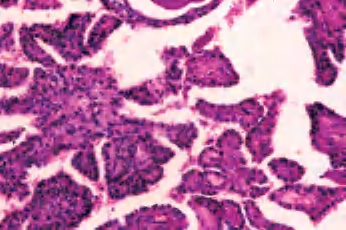

(1)滤泡亚型:由小至中等大小、不规则滤泡形成,实际上不含乳头结构,滤泡内含胶质,构成滤泡的上皮细胞有大而亮的核,含核沟和核内假包涵体。大约1/3此类肿瘤有包膜,预后与通常的乳头状癌相似(图3-44、图3-45)。

图3-44 甲状腺乳头状癌,滤泡亚型

图3-45 甲状腺乳头状癌,滤泡亚型